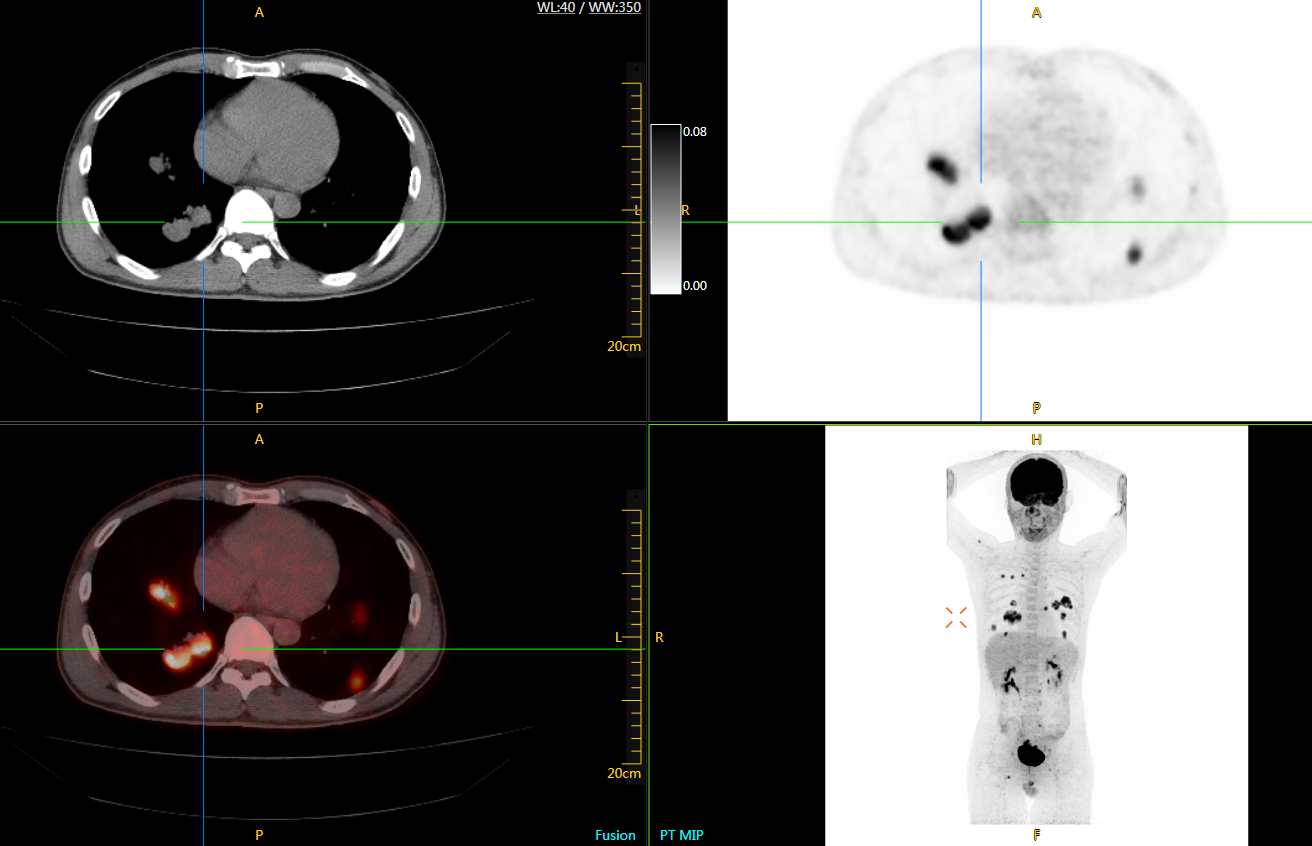

uExplorer探索者不再局限于傳統(tǒng)靜態(tài)代謝過程3D成像,而是在此基礎(chǔ)上新增一個維度——時間,從而實現(xiàn)4D全景成像。

注射總劑量為7.8mCi,14分鐘全身采集時間,在擁有超高靈敏度與超高分辨率的uEXPLORER上,即可得到展示顯示人體諸多精細結(jié)構(gòu)的高清三維圖像。

注射總劑量為7.8mCi,注射后1.6小時,基于uEXPLORER探索者掃描1分鐘的圖像

注射總劑量為0.67 mCi FDG(低于常規(guī)劑量的十分之一),基于uEXPLORER探索者掃描15分鐘的圖像

注射總劑量為6.9mCi,注射后10小時,基于uEXPLORER探索者掃描14分鐘的圖像